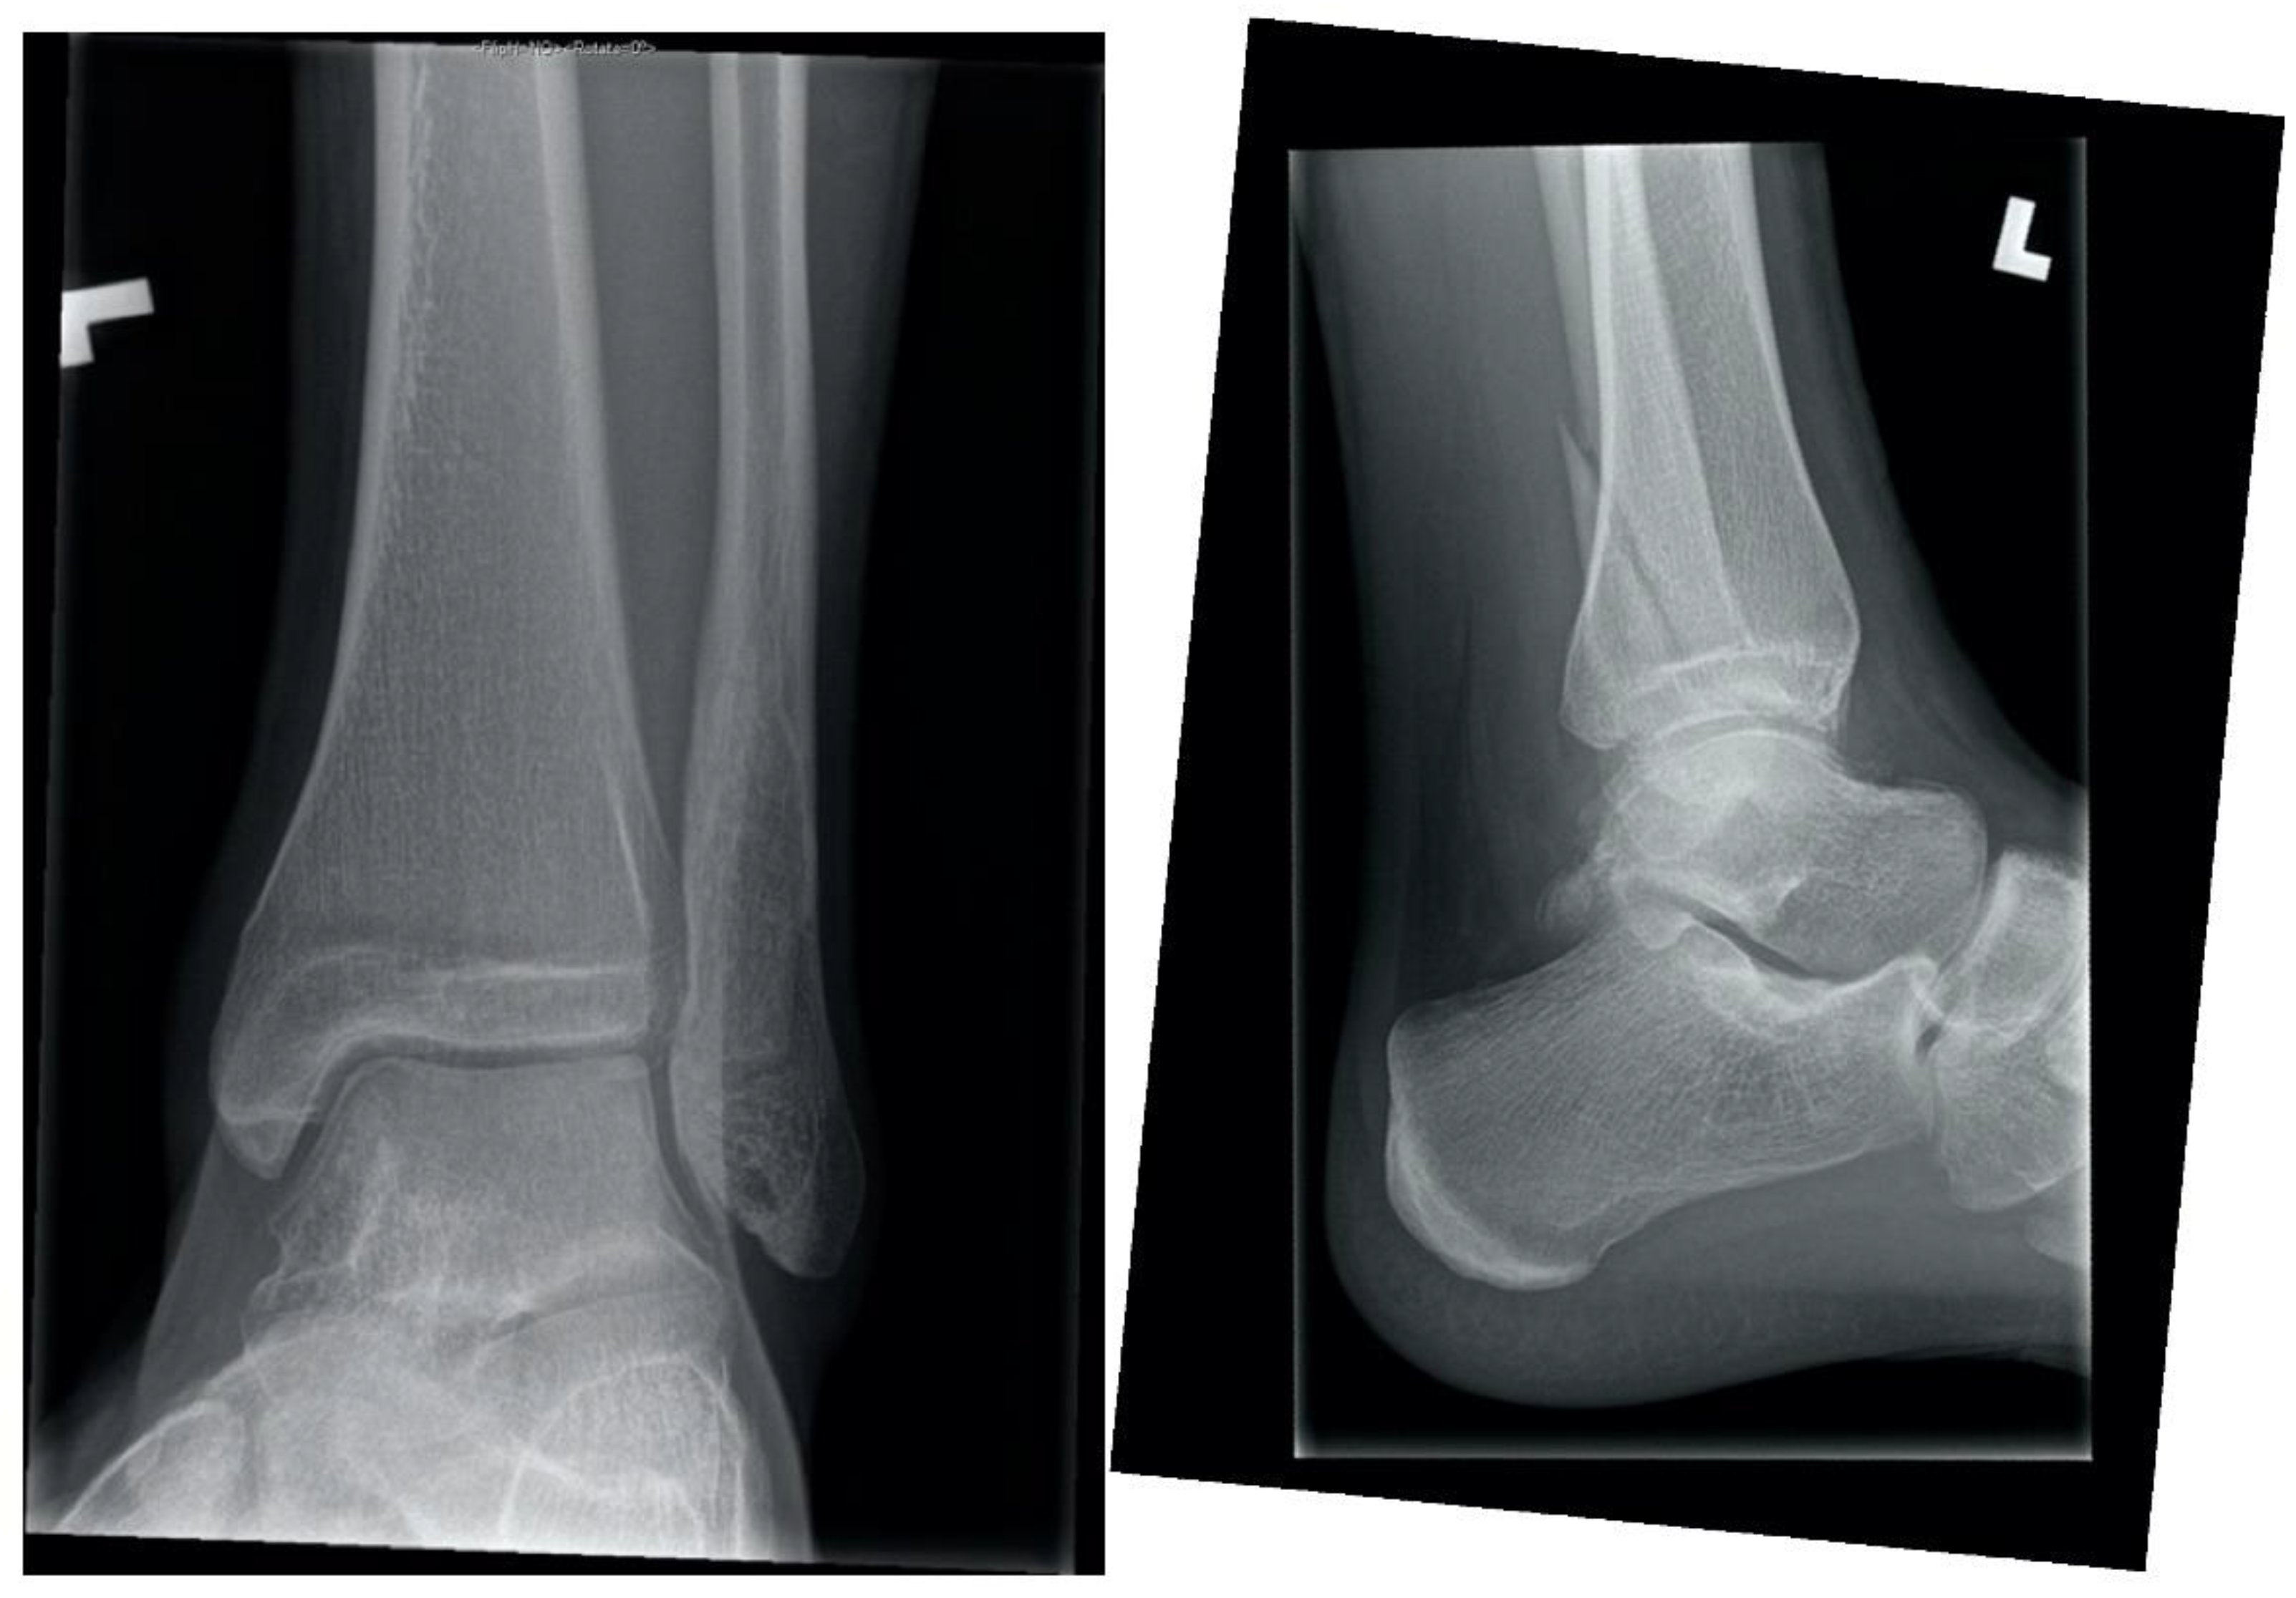

1.1. Ankle Fracture While Roughhousing, Eighteen Weeks in a 15-Year-Old Male